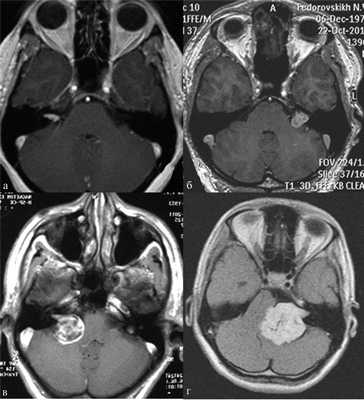

По результатам МРТ головного мозга правая пирамида височной кости деформирована, увеличена в объеме, выполнена субстратом размером до 5,5—2,8—3 см, распространяющимся на область внутреннего слухового прохода, заднего полукружного канала, медиальные отделы барабанной полости, сосцевидный отросток. Описанный субстрат изо-гипоинтенсивен в режиме Т1, гиперинтенсивен — в Т2 и non-EPI DWI (рис. 2). Заключение: признаки рецидива холестеатомы с деструктивными изменениями структур внутреннего и среднего уха на фоне хронических воспалительных изменений.

Рис. 2. Магнитно-резонансная томография головного мозга пациентки М. Деформированная, увеличенная в объеме пирамида височной кости выполнена мягкотканым субстратом.